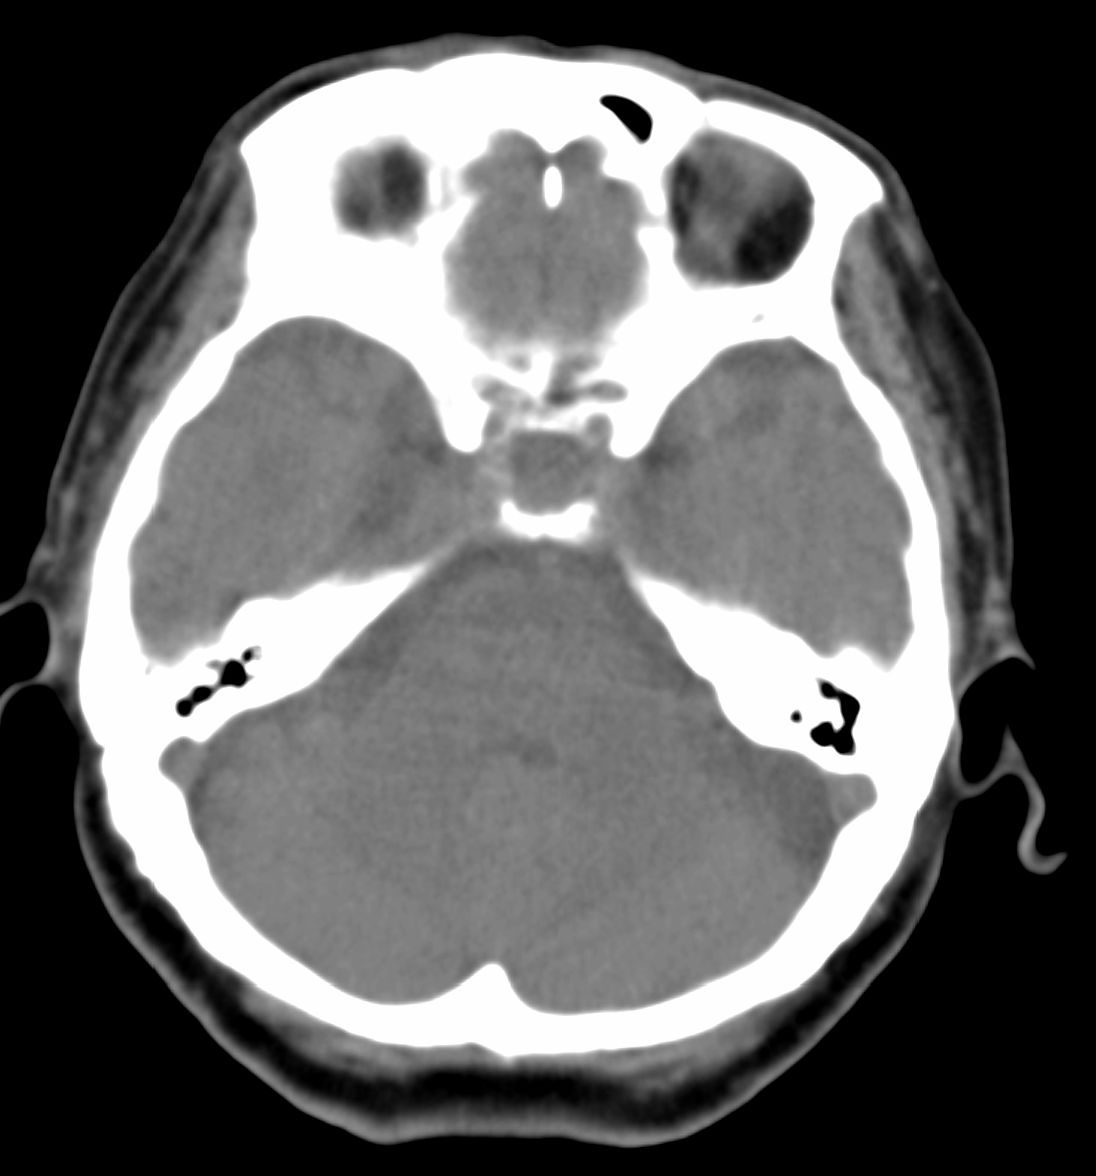

女,69岁。鼻出血2月多。(会诊病史就这样简单)鼻副窦ct检查如下:

左侧鼻腔及上颌窦见软组织块影,左侧上颌窦腔扩大,骨质吸收,右侧上颌窦见半圆形软组织密度影,鼻中隔向右侧弯曲,左侧鼻和鼻窦内翻型乳头状瘤可能性大,建议增强。

左侧上颌窦及鼻腔内见软组织密度影,其内密度不均匀,见斑片状高密度影,右侧上颌窦腔明显扩大,窦壁吸收变薄,鼻中隔右偏,右侧上颌窦见一半圆形软组织密度影,边界清楚,其内密度均匀。诊断,1、左侧鼻腔及上颌窦内翻乳头状瘤可能性大,上颌窦癌,息肉及霉菌性上颌窦炎待除外。2、右侧上颌窦粘膜下囊肿。

1)考虑左侧上颌窦内翻乳突状瘤突入左侧鼻腔。2)副鼻窦炎,右侧上颌窦黏膜下囊肿。

病理:霉菌性左侧上颌窦炎伴左侧上颌窦纤维组织增生。

窦腔密度不均匀增高,无明显钙化征象,后外侧及内侧窦壁膨胀明显,局部破坏消失,筛窦受累及,但双侧对比发现左侧窦壁骨质有硬化增白现象,这可能是支持左侧霉菌性上颌窦炎的主要依据点。